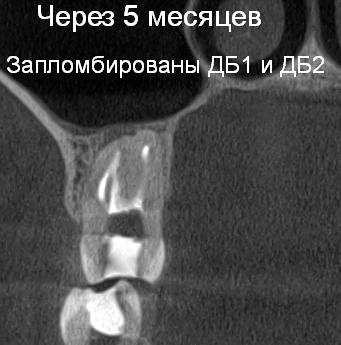

Так в следующем клиническом случае лечения апикального периодонтита мы наблюдаем очаг «воспаления» на верхушке проблемного зуба (рис. 10). Причина воспаления : инфекция в необработанных и незапломбированных каналах (рис. 11). После проведенной процедуры перелечивания системы корневых каналов (их оказалось 6, вместо ожидаемых 4!) под микроскопом мы убрали источник и воспаления и запустили иммунитет на восстановление костной ткани! На контрольных рентгенограммах мы наблюдаем полное восстановление от воспалительного процесса (рис 12).

Рис. 12 Контрольный снимок через 5 месяцев